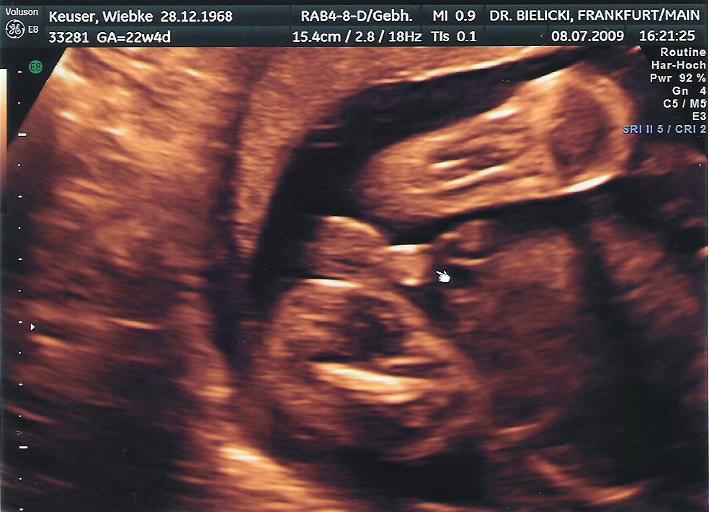

Das war das erste Bild von dir. Nun wussten wir von deiner Anwesenheit.

Irgendwann konnte man dann erkennen, dass du ein Mensch wirst (oder eher ein Teddy?)

.... erkennbare Strukturen....